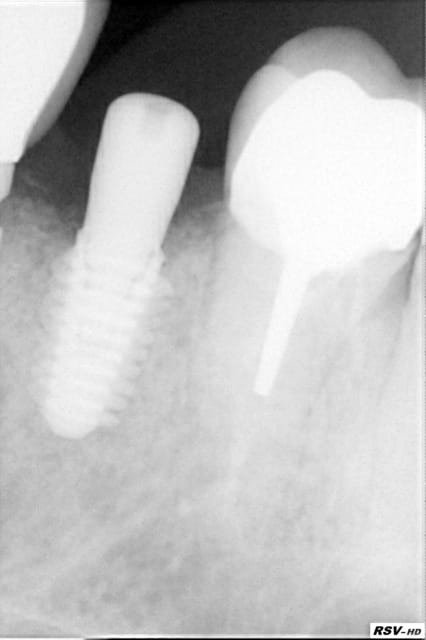

Le remplacement c'est fait par un AnyRidge de chez MegaGen de diamètre 5 et longueur 10. J'ai juste profiter de la situation pour re-combler là ou en 2007 on avait mis de l'os autogène....mais ou est il passé? Le comblement a été fait avec une recette maison à base de PRF os bovin et bétaTCP.

Voilà la rx post op elle ne passait pas dans le premier message.